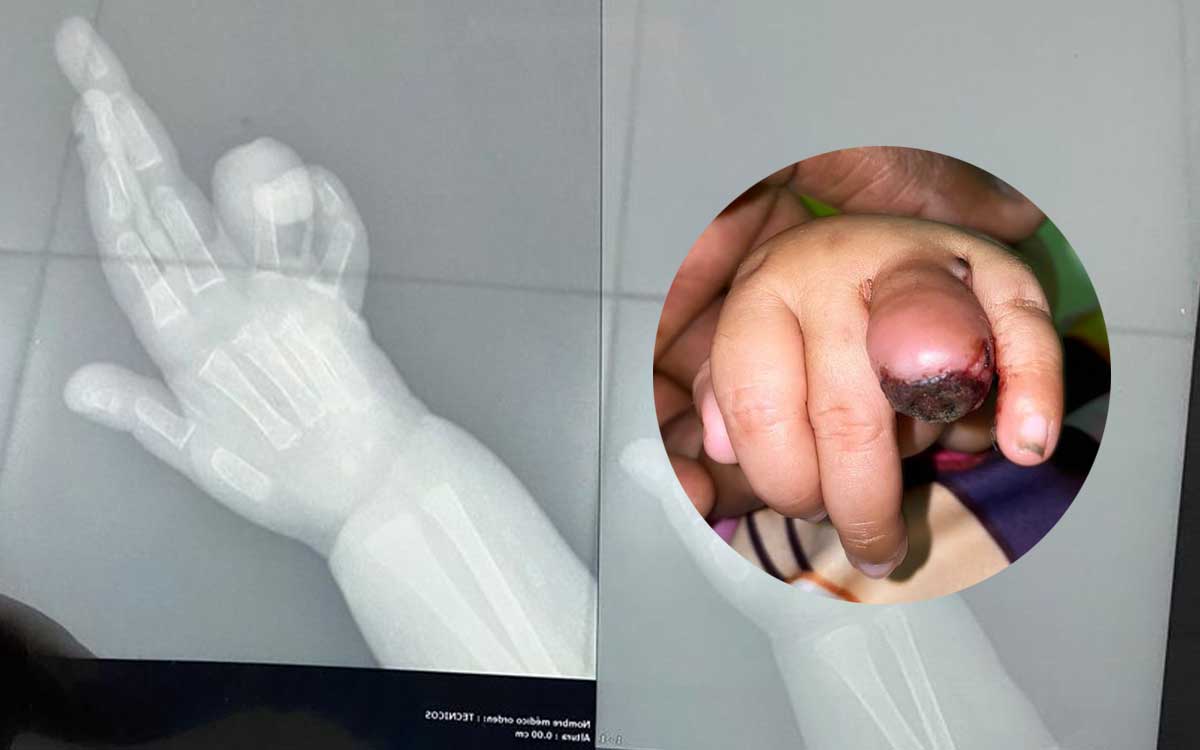

Una mujer denunció que dio a luz con cesárea en el Hospital Taiwan de Azua y cuando le entregaron a la criatura tenía su dedito “mochado” por la mitad y el personal médico le dijo que nació en esas condiciones.

La madre de la niña identificada como Dominga Ramírez, relató que “cuando recibió la bebé, su dedito estaba sangrando mucho y que la pediatra “cogió miedo”, tomó la criatura y se quedó con ella dos días”.

Asimismo, sostuvo que el personal sanitario no se hizo cargo, le dijeron “que la llevara al Hospital Pediátrico Robert Reid Cabral “Angelita”, que eso no “era nada”, lo cual la mujer acudió al centro referido y allí le informaron que el dedo de la niña había sido “mochado”.

La progenitora informó que la niña nació 10 de diciembre de 2021, es decir que tiene apenas cinco meses y aún no se le ha realizado una cirugía.